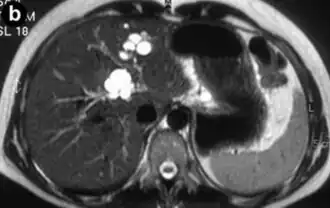

Ressonância magnética axial ponderada turbo spin-eco em T2 da doença de Caroli, mostrando dilatações císticas dos ductos biliares (mostradas em branco).[1] (Creative Commons Attribution 4.0 International License)

Doença de Caroli é um distúrbio hereditário raro caracterizado por dilatação cística (ou ectasia) dos ductos biliares no fígado. Existem dois padrões de doença de Caroli: a doença focal ou simples consiste em ductos biliares anormalmente alargados que afetam uma porção isolada do fígado. A segunda forma é mais difusa e, quando associada à hipertensão portal e fibrose hepática congênita, é frequentemente chamada de "síndrome de Caroli".[2] As diferenças subjacentes entre os dois tipos não são bem compreendidas. Também está associada a insuficiência hepática e doença renal policística. A doença afeta cerca de uma em 1 milhão de pessoas, com mais casos relatados de síndrome de Caroli do que de doença de Caroli.[3]